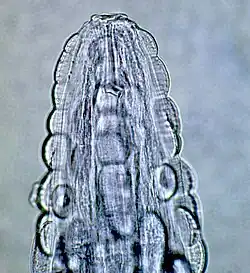

| Mannetjes Gongylonema pulchrum, afkomstig van een geïnfecteerde mens | ||||||||||||

Het voorste uiteinde bij beide geslachten is bedekt met talloze cuticulaire plaatjes met bij de nek een paar laterale papillen. De kleine mondopening verwijdt zich in de dorsoventrale richting. Rond de mond zit een cuticulaire verhoging, die de lippen omsluiten. Ook zitten er acht papillen laterodorsaal en lateroventraal rond de mond. Er zijn twee grote laterale amfiden. Aan de zijkanten van de staart van het vrouwtje zitten fasmidale (zintuig) openingen. Het staartuiteinde van het mannetje is asymmetrisch gevleugeld met 10 paar papillen en twee fasmidale openingen.[2] De gemiddelde lengte van het mannetje is 29,1 mm en dat van het vrouwtje 58,7 mm. De rondworm is zeer mobiel.